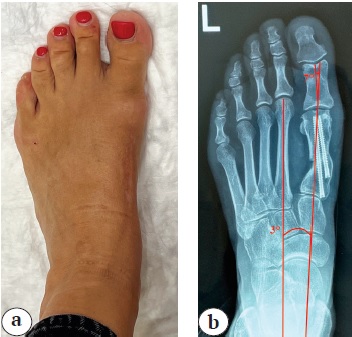

Пациентка 48 лет с приобретенной деформацией переднего отдела левой стопы. На момент осмотра перед операцией предъявляла жалобы на боли в области деформации. Жалобы сохранялись на протяжении года перед обращением. Выполнены рентгенограммы стопы с нагрузкой (рис. 2). Для оценки степени коррекции деформации измерялись первый межплюсневый угол и угол отклонения первого пальца — они были равны 13,5° и 25° соответственно.

Рис. 2. Стопа до операции: a — внешний вид; b — рентгенограмма с нагрузкой в прямой проекции

Fig. 2. Foot before surgery: a — general view; b — Stress X-ray in AP view

Установлен диагноз: комбинированное плоскостопие; приобретенная деформация переднего отдела левой стопы; вальгусная деформация первого пальца левой стопы средней степени тяжести.